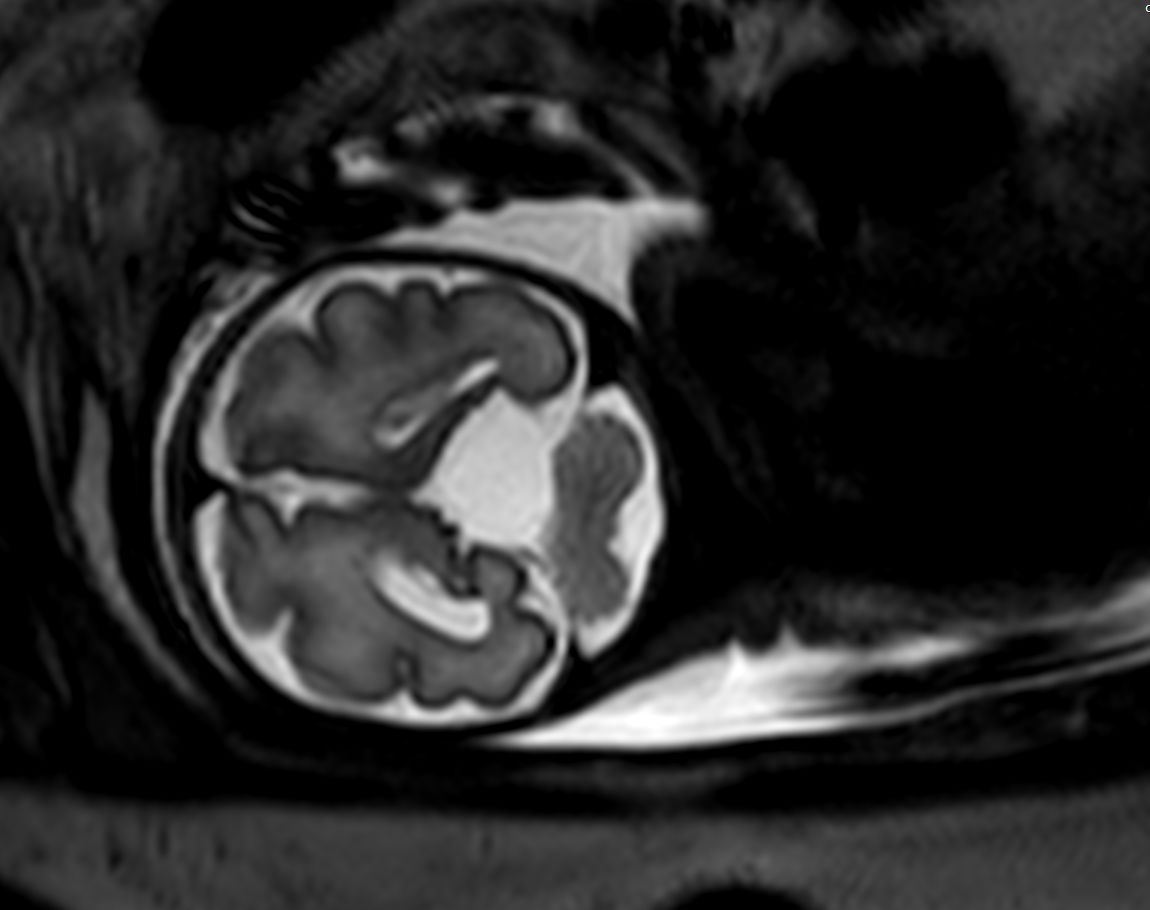

Pregnant patient, referred to MRI for fetal brain imaging because of suspected arachnoid cyst.

Coronal T2w TSE single shot